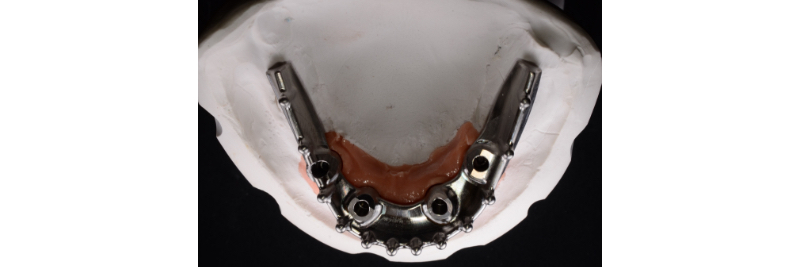

Master cast of four tissue-level analogs with soft tissue moulage.

CARES milled titanium bar on the verified master cast.

Front view of the milled titanium bar on the master cast.

Intaglio surface of the milled titanium bar.